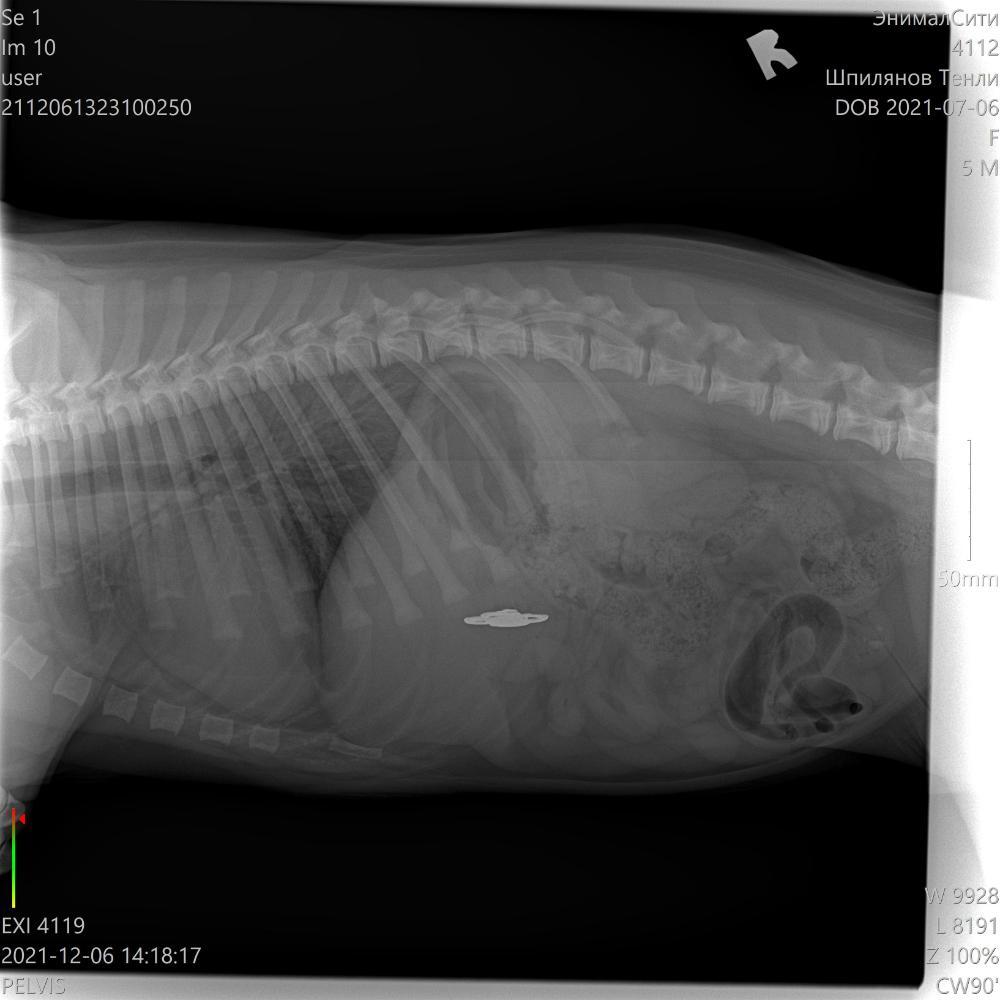

Иван Сергеевич Опубликовано 23 марта, 2022 Автор Опубликовано 23 марта, 2022 7 минут назад, Анна и любимый Бонд сказал: Если собака жрет все подряд, то инородку надо проверять в первую очередь. Рентген с контрастом. Да. Я вот думаю завтра настаивать в ветеринарке на нечто подобном. УЗИ или вот как вы подсказали. Она уже замечена была в том что жрет то что не должно жраться Вот два месяца назад. Хороша сама вышла. Брошка от шапки. Вот два месяйца назад

Иван Сергеевич Опубликовано 29 марта, 2022 Автор Опубликовано 29 марта, 2022 Откапались 5 дней. С Диагнозом после осмотра - панкреатит. Капали - физраствор, антибиотик, климател. Отошла. Начала носиться то се. Два дня погуляли. Все здорово. Вчера оба - и опять. Ни есть ни пить и лежит в лежку. Тоже самое. Капец. Поехали в другую клинику. Осмотр - тоже самое: никакого криминала. Биохимия - аминалаза норма. АЛТ - норма. АСТ - в три раза превышение. Врач говорит это не может быть панкреатит однозначно. Ставит острый гастрит + завтра УЗИ.